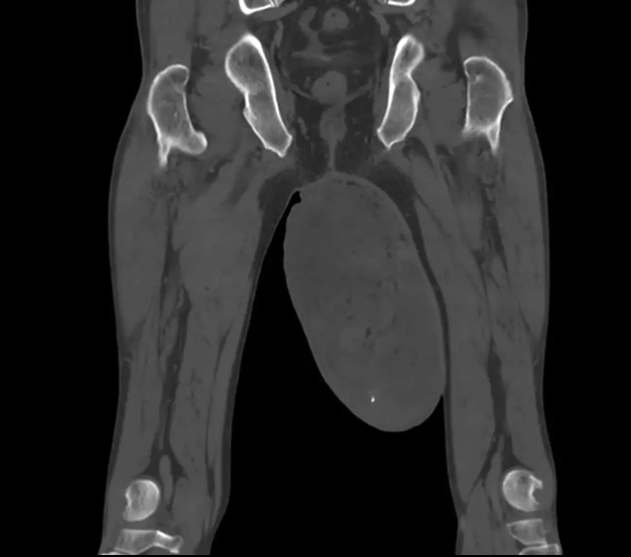

Ľavý semenník pacienta mal 123×168 milimetrovčo je tri- až štyrikrát viac ako normálna veľkosť. V jeho vnútri našli lekári dobre ohraničený, tuhý a hladký útvar. Zaujímavé je, že pacient netrpel žiadnymi inými zdravotnými problémami. Jeho BMI bolo 25, čo sa považuje za miernu nadváhu, no nie obezitu. Pravý semenník bol normálny a ultrazvuk neodhalil žiadne iné problémy s vnútornými orgánmi, píše na svojom portáli New York Post.

(Zdroj: BMC Urology)

Po operácii prišlo ďalšie prekvapenie. V prípade tohto pacienta išlo totiž o nezhubný nádor, známy ako angiomyofibroblastóm (AMF), ktorý sa bežne vyskytuje na ženskej vulve. Je taký zriedkavý, že v odbornej literatúre bolo u mužov zdokumentovaných len osem podobných prípadov. „Takéto nádory rastú veľmi pomaly a väčšinou bez bolesti, preto si ich pacienti dlho nevšimnú,“ vysvetlil tím lekárov v odbornej správe. Aj keď sa nádor veľkosti vajca zdá byť veľký, u žien môže dorásť do omnoho väčších rozmerov a zatiaľ najväčší dosahoval dĺžku 34 centimetrov.